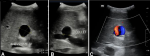

Diagnostic assessment: laboratory tests revealed microcytic hypochromic anemia (Hb 6.2 g/dL), low ferritin (6 µg/L), elevated C-reactive protein (11 mg/L), and positive HBs antigen. Doppler ultrasound demonstrated a saccular aneurysm with the characteristic 'yin-yang' flow pattern and mural thrombosis (Figure 1 A,B,C). CT imaging confirmed these findings, showing chronic partial thrombosis and marked splenomegaly with gastroesophageal varices (Figure 1 A,B).

Figure 1: ultrasound of the liver showing the portal trunk: A) intrahepatic portal vein aneurysm measuring 23 - 22 mm; B) aneurysm neck measuring 16 mm; C) color Doppler showing the typical “yin-yang” flow pattern within the aneurysm